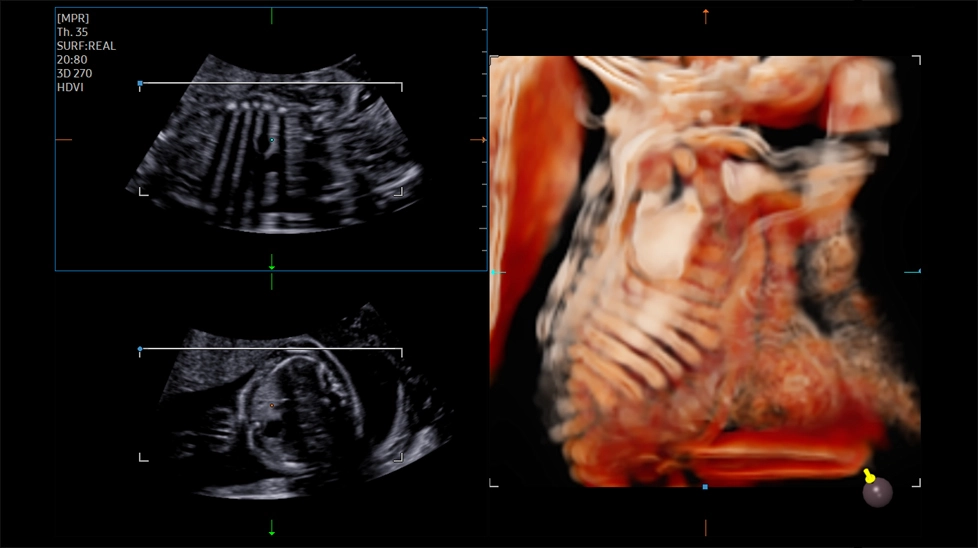

- HDVI (High Definition Volume Imaging) - повышение четкости изображения границ тканей с разной эхо-плотностью в объемном изображении (диагностика тонких повреждений тканей, дефектов мозга плода, стенок и клапанов сердца плода).

- CrystalVue - программа реконструкции прозрачного 3D УЗИ, которое получается при одновременном усилении внутренних и наружных структур. Применяется для визуальной оценки состояния плода и матки, помогает лучше идентифицировать мягкие ткани и кости

- RealisticVue - программа реконструкции реалистичного 3D УЗИ, при котором на объемное изображение накладывается виртуальный источник освещения. Специальный процессинговый алгоритм воспроизводит трехмерную анатомию плода с исключительной детализацией

Ребра и лопатка плода с CrystalVue

Позвоночник плода с CrystalVue